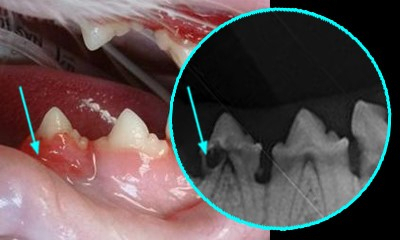

고양이의 대표적인 구강질환으로는 잇몸구내염, 치아흡수증, 구강인후두염 등이 있다. 이 질병들은 잇몸과 구강 점막에서 면역을 담당하는 면역세포가 비정상적으로 활성화되어 자신의 치아를 녹이거나 염증을 만성화시키는 특징이 있다. 심각한 구강염증은 호흡을 통해 폐의 세균 감염을 유발하기도 하며 염증 주변의 모세혈관으로 세균이 침투하여 혈전과 패혈증을 유발하기도 한다. 대부분 장기간 약물치료가 필요하며 심각한 경우 전체 치아를 발치해야 하는 경우도 있다.

사료와 간식에 포함된 탄수화물은 치태를 만들고 그 표면에 미네랄이 침착되어 치석이 된다. 치석은 일단 형성되면 양치질로 제거할 수 없으며, 치아와 잇몸 사이에서 세균 증식이 용이하게 만들어 만성 구내염과 치주질환을 발생시키는 가장 큰 원인이 된다.

고양이 치아표면에 치태와 치석이 관찰되거나, 잇몸이 빨갛게 부어있거나, 통증을 호소한다면 수의사에게 구강검진을 받길 바란다. 구강 질환이 확인된 고양이는 일 년에 1회 이상 정기적으로 검진을 받고 스케일링과 잇몸치료를 받아야 한다.